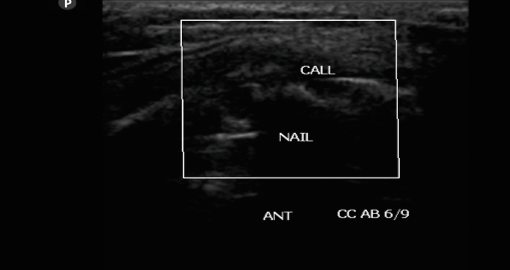

OSSEOUS STAGE : Echogenic callus with acoustic shadowing and obscured medullary cavity / IM nail …5-6 wks

Fracture of long bones and in particular of tibia has remained a bane for most of the orthopedicians since they land up with frequent delayed and non-unions. Till date there is no modality except a skiagram which can predict union but not before 12 weeks... High frequency ultrasound has come to establish itself as the modality which can predict delayed union as early as 4 weeks and non-union at 7-8 weeks. Interlocking which is the mainstay of management for fracture shaft tibia today can be effectively managed early by dynamizing at 4weeks in case of delayed union , or in case of infections reaming with exchange nail at 6 weeks to save the patient the catastrophe of a non-union or osteomyelitis. Both grey scale imaging and colour doppler imaging act in a symbiotic manner to give a high predictability rate for union/ nonunion or delayed union in cases of fracture healing.